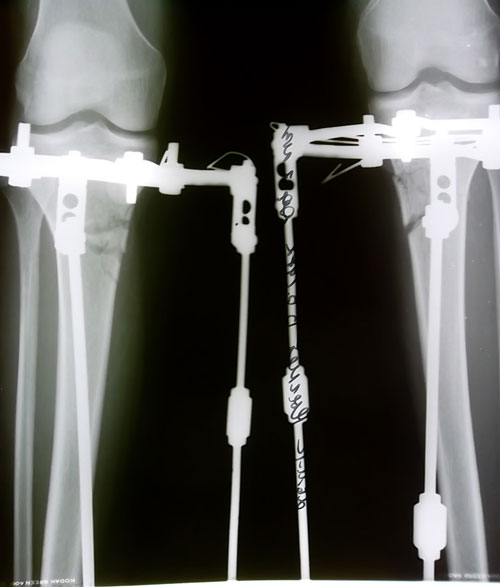

- Диагноз: О-образная деформация ног

- Вид проведённой операции.: поперечно-фрагментар

- Дата операции.: 0- 3-2011

- Срок лечения.: 2,5 месяца

- Оценка результата операции.: супер довольна

- Диагноз: О-образная деформация нижних конечностей

- Дата операции.: 06.11.2012

82 дня со дня операции.

Форма ножек отличная! Видно, что Вы много ходите, потому что стал появляться внутренний контур голени, который делает ножки ещё лучше.

Ждём фото через 2 недели.